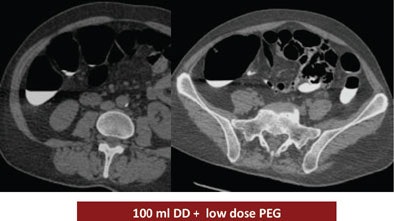

The study looked at three groups of 30 patients who underwent virtual colonoscopy after a same-day bowel preparation. Group 1 ingested 200 mL of undiluted DD the day of the exam, group 2 drank 100 mL of the agent the day of the exam, and group 3 ingested a low-dose polyethylene glycol (PEG) formula (macrogol) the two days before the exam, followed by 100 mL of DD the day of the exam.

| Judged subjectively, the best overall prep quality was found in group 1, followed by group 3, with the worst results in group 2. By segment, the largest differences in quality were found in the cecum, with mean quality scores of 2.3 for group 1, 1.6 for group 2, and 3 for group 3. All images courtesy of Dr. Riccardo Ferrari. |

Group 1 had the best-quality results, with well-marked colonic mucosa but significant residual fluid. The use of 100 mL DD combined with low-dose polyethylene glycol over two days may have improved fecal tagging by softening the stool before the ingestion of the iodinated agent. In addition, no side effects were reported among the patients who ingested the PEG preparation for two days before the exam (group 3), Ferrari said.

| Above, the use of 200 mL DD in group 1 yielded the highest quality scores. While the colonic mucosa was well marked, significant volumes of fluid remained in the colon, similar to the 100 mL DD preparation (group 2, below). The use of 100 mL combined with low-dose polyethylene glycol over two days (bottom image) may have improved fecal tagging by softening the stool before the ingestion of DD. |